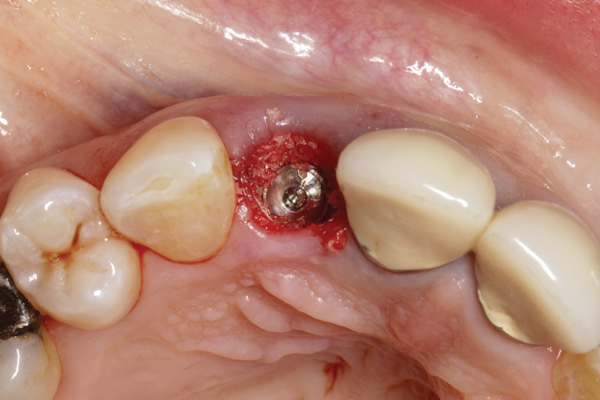

When placing an implant in the esthetic zone, ideal 3-dimensional positioning, including mesio-distal, apico-coronal, and orofacial dimensions, is essential to achieve favorable esthetic outcomes, regardless of the implant system used (Figure 6).45 With respect to the orofacial dimension, implants should be placed in a more palatal or lingual position to allow the presence of at least 2 mm of buccal bone thickness from the implant buccal shoulder.45,46 When the distance of the buccal bone wall and implant buccal shoulder is < 2 mm, a significantly higher incidence of midfacial recession has been previously reported.3,12 Placement of bone graft (Figure 7) and immediate restoration (Figure 8 and Figure 9) at the time of implant placement has also been suggested to increase peri-implant soft-tissue height and thickness.51 In the apico-coronal dimension, the implant head should be at least 3 mm apical to an imaginary line connecting the CEJ of the adjacent teeth and 1 mm to 2 mm apical to the interproximal and crestal bone to ensure a proper implant emergence profile and facilitate proper implant restoration (Figure 10). Regarding the horizontal implant–tooth distance, implants should be placed no closer than 1.5 mm from the adjacent root surface to minimize resorption of the interproximal alveolar crest, which causes a reduction in the papillary height.46,52